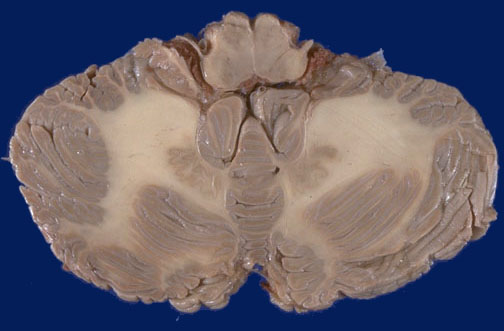

Identify the following regions of the normal brain by clicking in the image below:

Dentate nuclei - IX cranial nerves - Pyramids of medulla oblongata